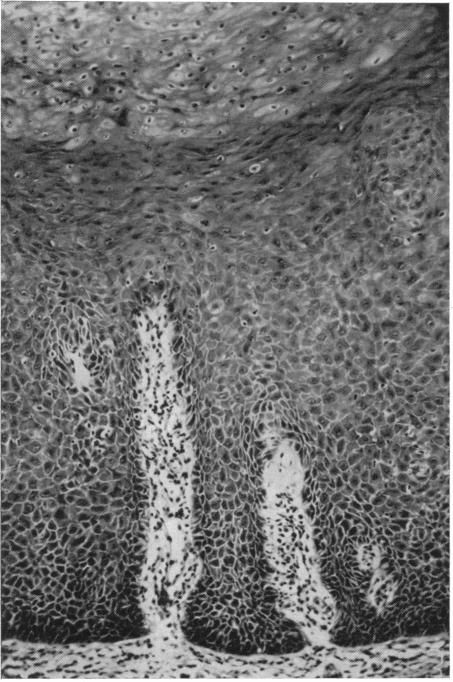

COOKE B E

Ann R Coll Surg Engl. 1964 Jun;34(6):370-83.